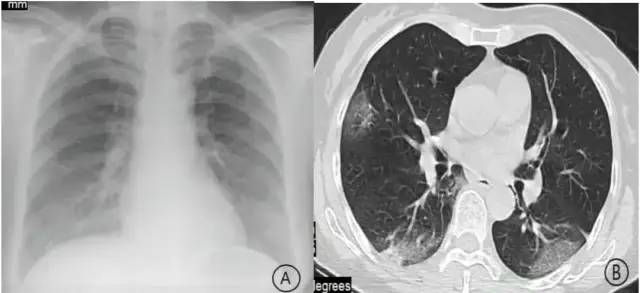

甲流将导致重度肺炎

此次肆虐的甲流病毒,曾在2009年引发了26%的重症病死率,其中孕妇死亡率达40%!

目前已有的病例统计中,老年人、儿童、孕妇和有基础疾病的人群均是“白肺”的高发人群。

从网友们的描述来看,甲流患者多出现了咳嗽、咽喉痛、高热等症状,同时伴有头痛、肌肉酸疼等全身不适。但看这些症状,与新冠症状并无不同之处。那么,又该如何判断自己是得了甲流还是新冠呢?

武汉大学的研究发现,新冠病毒进入肺泡细胞后,将导致肺泡受损,而感染流感后的细胞通过一系列反应表达,打开了新冠病毒侵入肺泡细胞的大门。